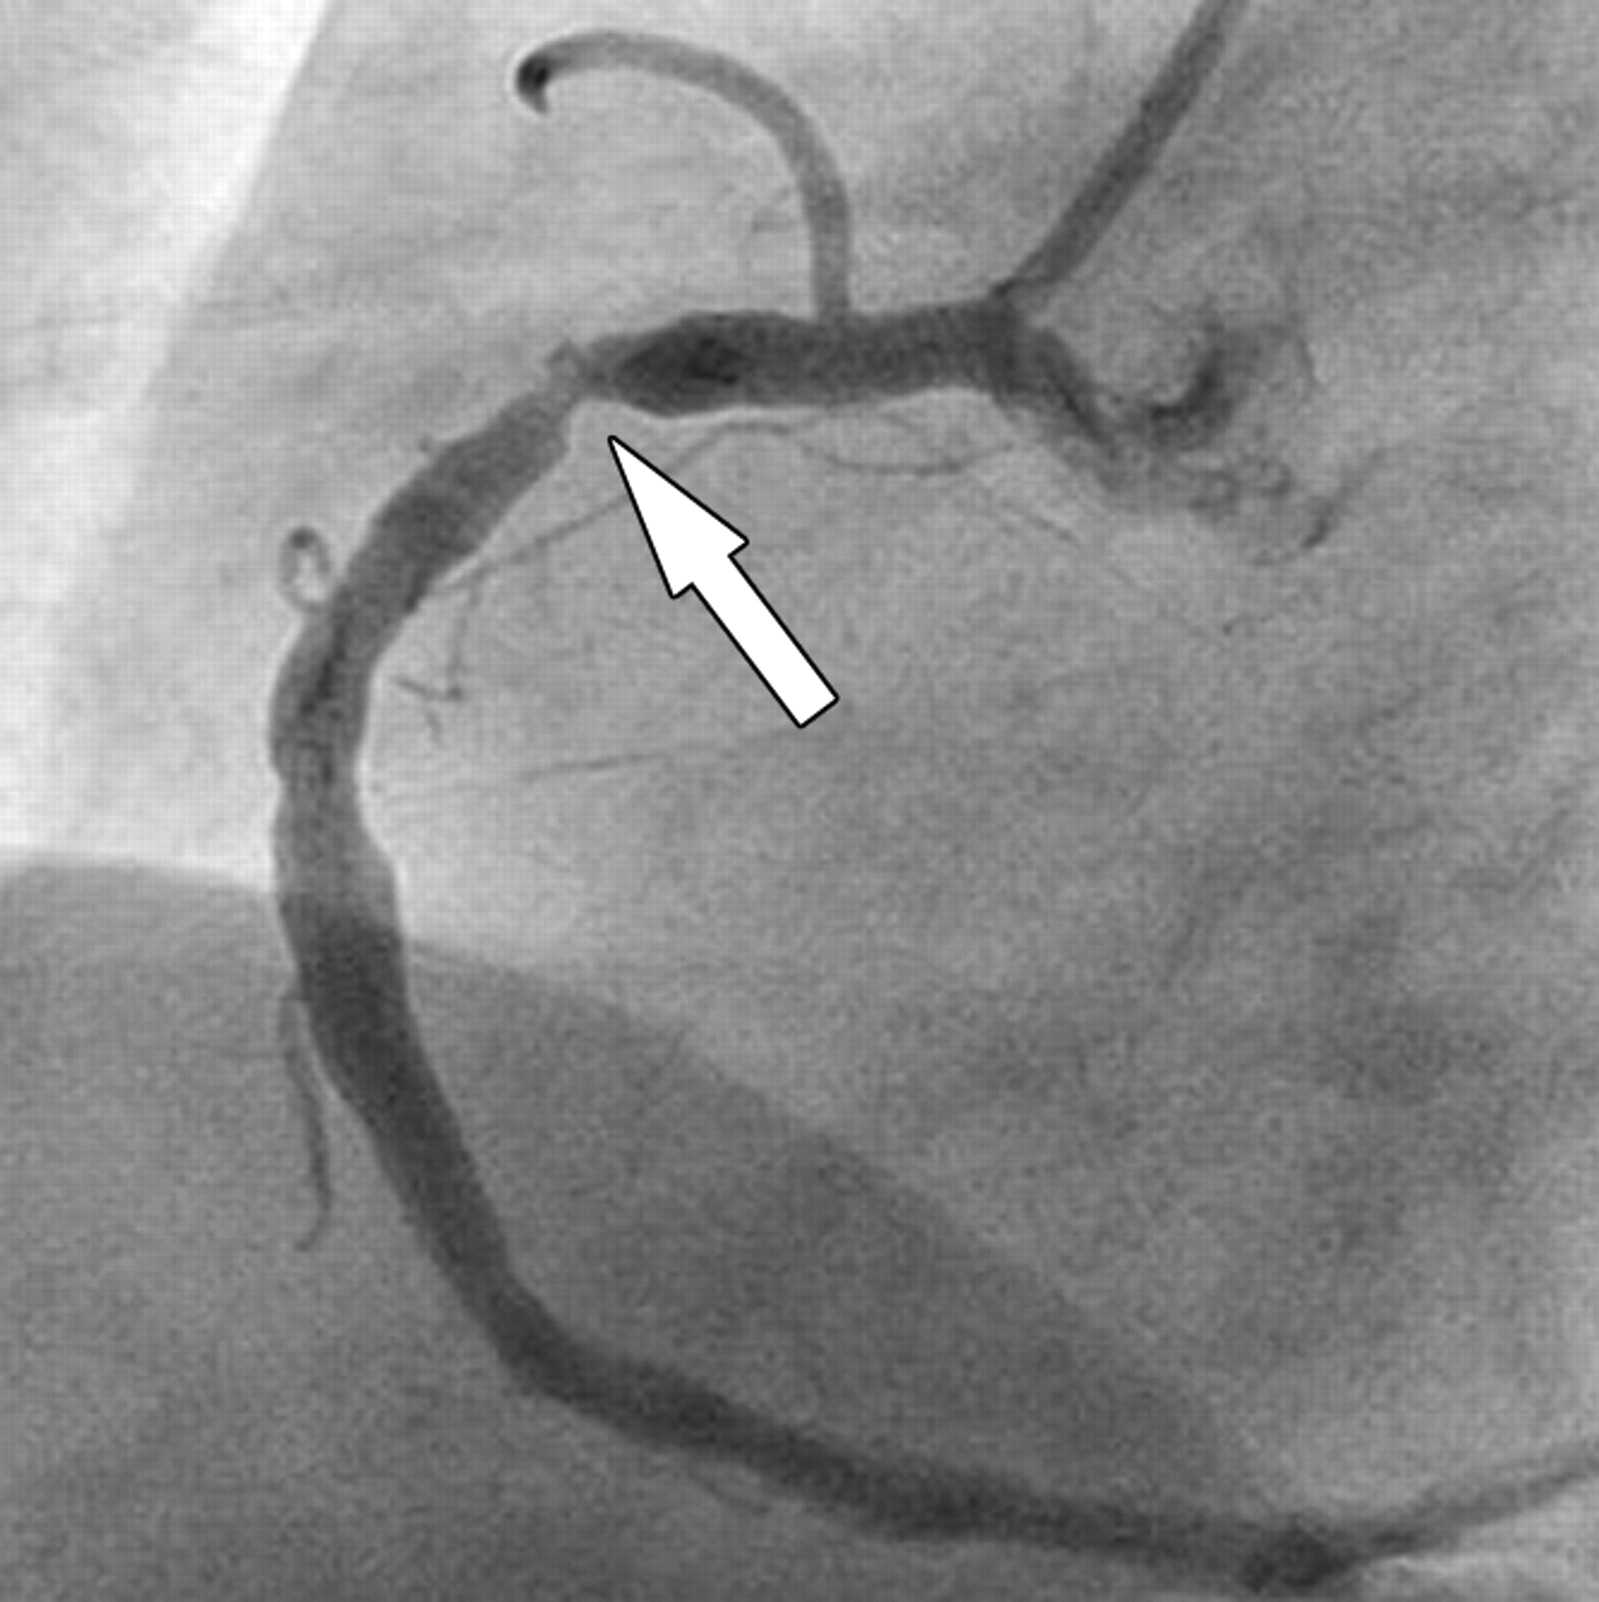

Коронарография сердца: доступы, техника пункции артерий и основные этапы исследования

КОРОНАРОГРАФИЯ СОСУДОВ ЛЕВОЙ СЕРДЕЧНОЙ АРТЕРИИ